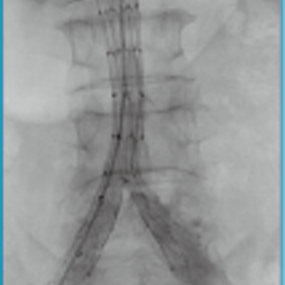

Aegis®/定海石™分叉型大动脉覆膜支架及输送系统

Aegis®/定海石™分叉型大动脉覆膜支架及输送系统适用于瘤体累及髂总动脉的腹主动脉瘤的治疗。